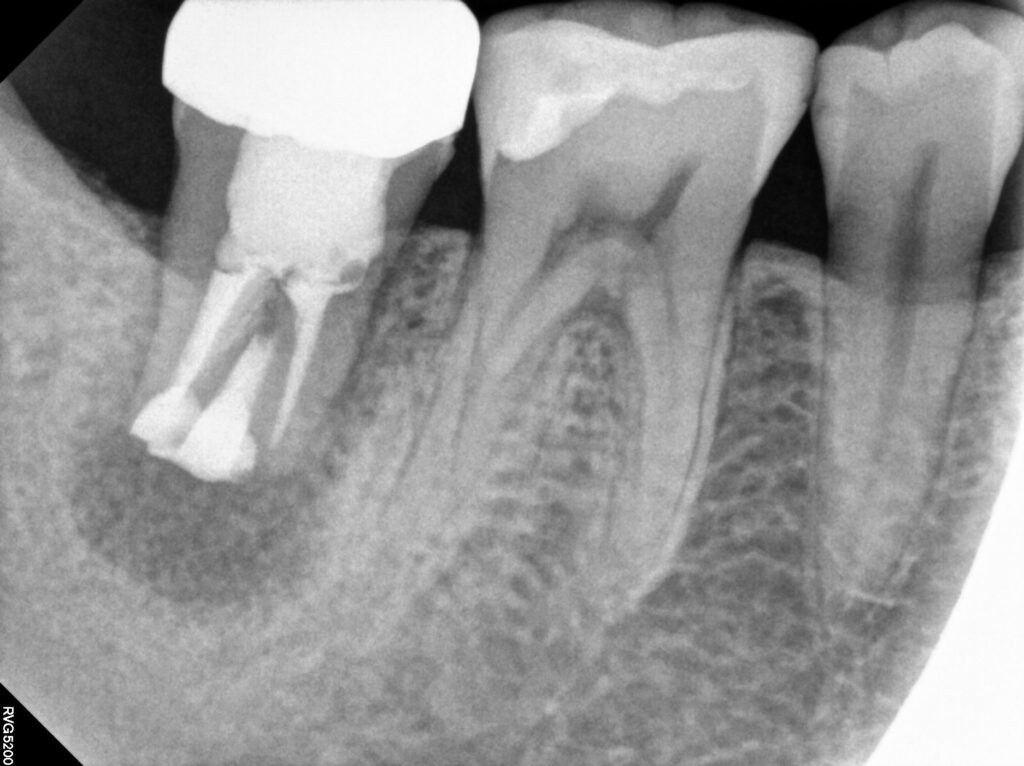

엑스레이를 보았을 때

치아 뿌리 끝 염증이 이환되어

큰 염증이 나타난 것을

관찰할 수 있는데요.

방사선 사진에서는

치근단 부위의 어두운 음영이

뚜렷하게 나타나며

주변 골조직의 파괴가

상당히 진행된 것을

확인할 수 있습니다.

치아재식술 후 4개월까지 경과 모습으로,

엑스레이 사진에서는 기존 염증 부위가

점점 건강한 뼈조직으로 채워지고 있는 것을

명확하게 확인할 수 있습니다.

치조골이 생성되면서

동요도가 사라졌고 불편했던 느낌도

모두 해결된 것을 확인할 수 있습니다.

이는 재식술이

성공적으로 이루어졌음을

보여주는 소견이었습니다.